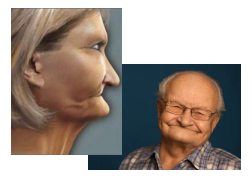

Bone grafts or your face will collapse

keep that secret under wraps